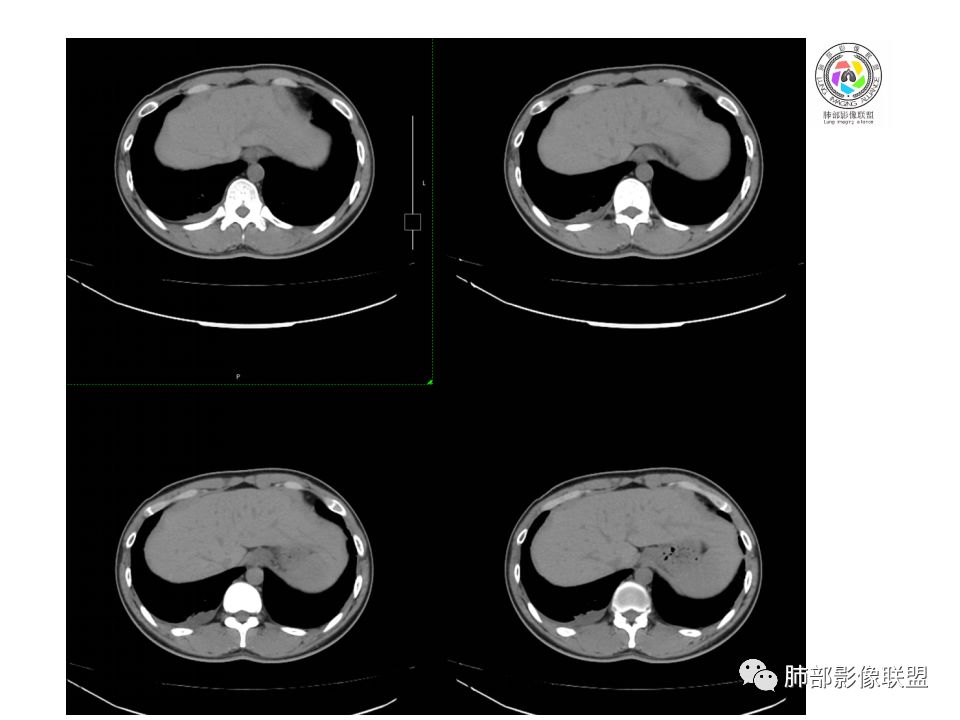

右前上纵隔占位,瘤肺交界面清楚,提示纵隔来源,其内有点状钙化,右侧胸腔积液,有临床症状,年龄轻,考虑生殖来源可能,胸腺瘤待排,请结合临床相关检查或CT增强进一步检查。

左肺上叶病灶,陈旧性钙化灶,右侧胸水是否与之相符,结核?

前纵隔右区占位性病变,上区与胸腺延续,下区呈分叶状,尽管年龄<30还是首先考虑胸腺瘤,侵袭性可能性大(眼睑下垂不知是否有关)。鉴别主要是生殖细胞类肿瘤,主要是精原细胞瘤。另左肺上叶结核球,右侧胸腔积液,需除外结核性胸膜炎和转移

右前纵隔肿块,边界清楚,密度欠均匀,内似有分隔和低密度区,似有多结节融合,几乎从上到下,年龄较轻,不是胸腺瘤好发年龄,但却有视物模糊,眼睑下垂症状,考虑淋巴瘤?鉴别胸腺瘤?结核?